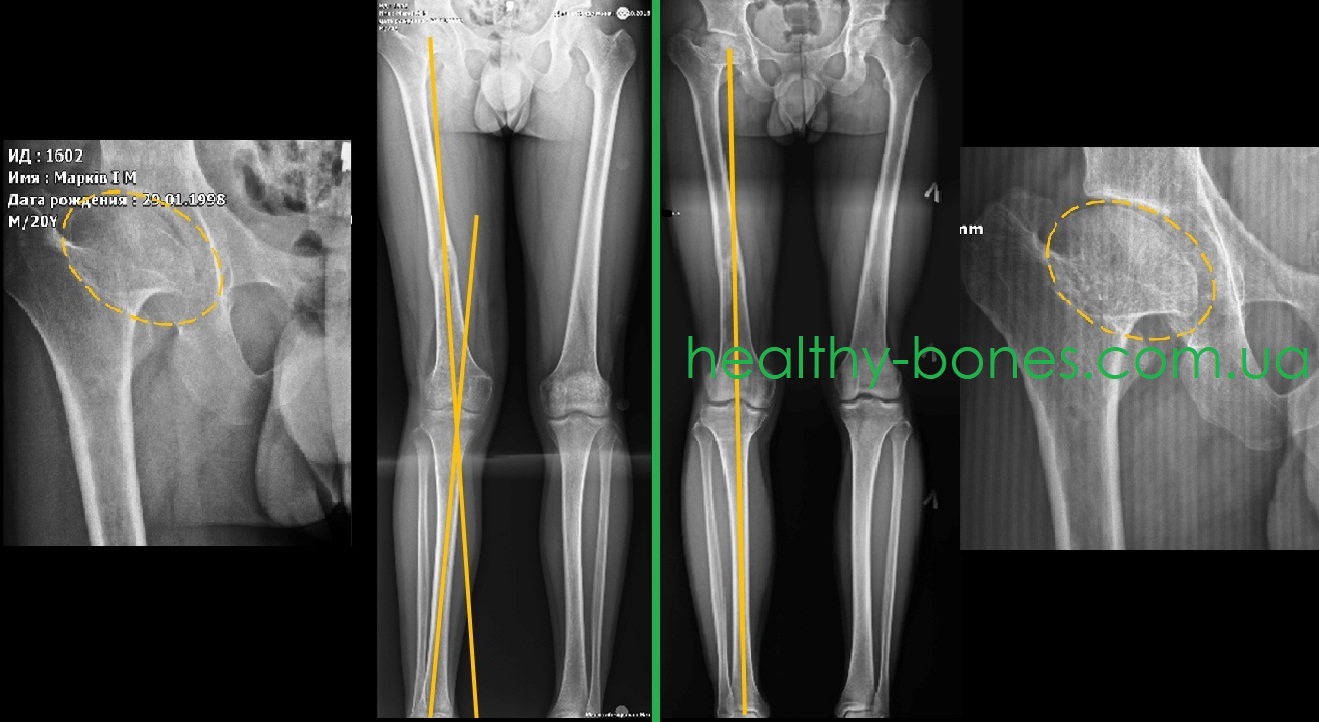

- значне скорочення шийки правої стегнової кістки з грибовидню деформацією голівки, шийково-діафізарний кут в межах 130°

- вкорочення правої нижньої кінцівки до 5 см

- вальгусна деформація гомілки.

Ми провели етапне оперативне лікування — на першому етапі виконано подовження правої стегнової кістки, а на другому — усунена вальгусна деформація гомілки.

Дані операції дозволили максимально можливо відновити осьове навантаження правої нижньої кінцівки, що дозволило усунути больовий синдром в області правого кульшового суглоба. Після завершення лікування голівка стегнової кістки стала більш округлою, що сприяло збільшенню обсягу рухів в суглобі.